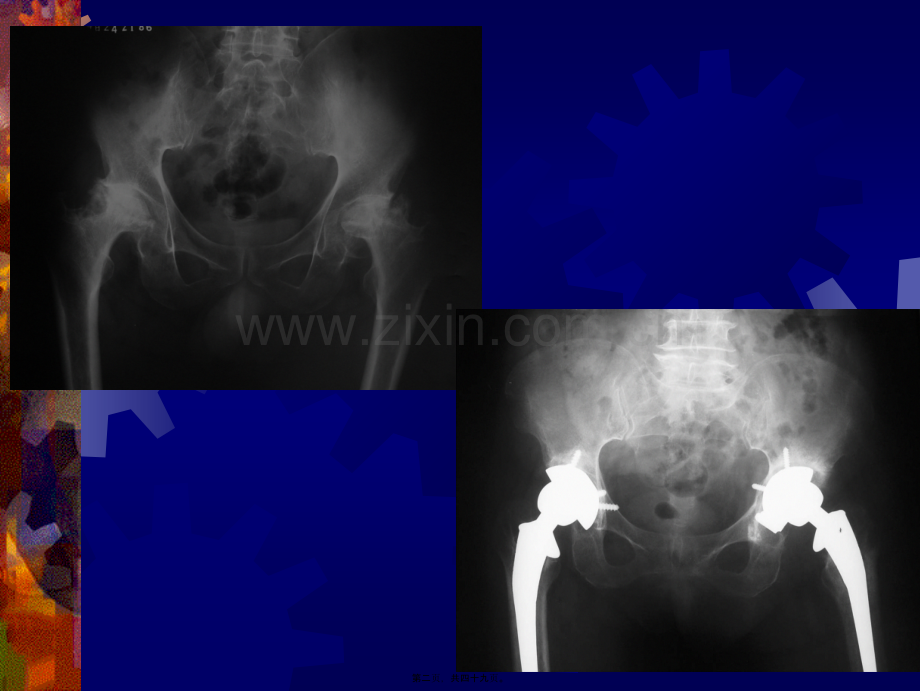

人工髋关节置换是指由伤病引起的髋关节功能障碍而采用人工设计(shj)的假体替代材料植入体内以改善关节功能提高生活质量的外科介入的方法,其术后的康复治疗对其功能的恢复有着重大的影响。概 念第一页,共四十九页。第二页,共四十九页。一、康复训练的原则一、康复训练的原则(yunz)(yunz)第三页,共四十九页。个 性 化 原 则(yunz)伤病种类 体质差异 手术方式 康复训练的原则(yunz)第四页,共四十九页。循序渐进原则 术后不同时间段康复方法不同,从易到难,从简单到复杂 病情(bngqng)恢复快慢 有无并发症出现康复训练的原则(yunz)第五页,共四十九页。局部与全身相结合原则 关节各运动(yndng)单位 相邻关节 上肢与下肢 躯干与四肢 康复训练的原则(yunz)第六页,共四十九页。二二、术术前前康康复复教教育育(jioy)(jioy)及及准准备备第七页,共四十九页。术前健康(jinkng)教育及准备病人要了解一般情况 伤病的预后 手术的方法(fngf)及预后 可能出现的问题 康复的时间第八页,共四十九页。术前健康教育(jioy)及准备术前健康(jinkng)教育及准备 训练病人深呼吸、咳嗽 床边训练排二便第九页,共四十九页。术前健康教育(jioy)及准备病人(bngrn)要树立康复 信心 恒心 小心第十页,共四十九页。三、术后的治疗三、术后的治疗(zhlio)(zhlio)护理护理第十一页,共四十九页。1伤口(shngku)放置引流24-72h2早期平卧、髋外展300、穿防旋鞋3抬高患肢、伸屈踝关节、使用下肢 静脉泵术后的治疗(zhlio)护理第十二页,共四十九页。4适当使用(shyng)镇静止痛 静脉镇痛 硬膜外阻滞镇痛 术后的治疗(zhlio)护理第十三页,共四十九页。5常规(chnggu)应用抗生素8-10天6鼓励排痰,多饮水、多食粗纤维食 物及维生素术后的治疗(zhlio)护理第十四页,共四十九页。四、术后的康复训练四、术后的康复训练第十五页,共四十九页。根据身体恢复状况分阶段进行(一)住院期间的康复训练1术后第1-3天,以促进下肢血液回流,防止血栓形成(xngchng)为主的康复措施,达到基本消除肢体肿胀,各组肌群能协调舒缩术后的康复训练第十六页,共四十九页。方法(术后第1-3天)屈伸踝关节5-10次/h,每一动作(dngzu)持续3秒转动踝关节3-4次/d,每次重复5遍健侧伸屈髋膝一组/2h、30次/组,每次持续10秒。住院(zh yun)期间康复训练第十七页,共四十九页。第十八页,共四十九页。2术后第4-7天此期病人已可进食,体力渐恢复训练以增强(zngqing)肌力、恢复髋关节活动为目的住院(zh yun)期间康复训练第十九页,共四十九页。方法(术后第4-7天)每天3-4次,每次10遍重复练习(linx)伸髋、膝臂部收缩髋外展股四头肌收缩直腿抬高髋后伸住院(zh yun)期间康复训练第二十页,共四十九页。第二十一页,共四十九页。第二十二页,共四十九页。第二十三页,共四十九页。3术后第8-14天此期以增加关节活动度髋关节主动屈曲(q q)达900为目的。住院(zh yun)期间康复训练第二十四页,共四十九页。方 法(术后第8-14天)下地练习(linx)术侧与骨盆平行移动下坐练习 屈髋900,高椅子站立练习 患侧在前、健侧在后站立抬腿 扶手站立患肢抬高、以上每项3-4次/天站立后伸练习 每天3-4次,每次2-3遍住院(zh yun)期间康复训练第二十五页,共四十九页。第二十六页,共四十九页。第二十七页,共四十九页。第二十八页,共四十九页。第二十九页,共四十九页。第三十页,共四十九页。第三十一页,共四十九页。术后15-21天 此期由助行器(xn q)过渡到扶腋杖住院期间康复(kngf)练习第三十二页,共四十九页。方法(fngf)(15-21天)助行器双侧腋杖站立稳步后,可扶助行器 待重心稳定,改用腋杖 3-4次/天、5-20分钟/次住院(zh yun)期间康复训练第三十三页,共四十九页。第三十四页,共四十九页。术后第21天以后(yhu)第三周扶双腋杖第六周扶单腋杖第九周弃拐行走住院(zh yun)期间康复训练第三十五页,共四十九页。(二)出院康复训练 以站立(zhn l)及行走练习为主第三十六页,共四十九页。1由助行器改为双腋拐行走时间(shjin):术后第14-21天 非骨水泥全髋置换适当延长时间出院康复(kngf)练习第三十七页,共四十九页。方法:双拐前移1足距离 重心越过双拐连线 健侧前移越过双拐连线 20-30cm如此(rc)交替进行出院(ch yun)期间康复训练第三十八页,共四十九页。第三十九页,共四十九页。2继续站立抬腿及后伸练习方法 患侧在前、健侧在后 扶手(f shou)患肢向前抬起(屈髋屈膝)及向后抬起出院(ch yun)期间康复训练第四十页,共四十九页。上下楼练习(linx)大部分患者术后第21天可以练习方法:上楼梯时健腿先迈上台阶,再将术侧跨上 下楼梯时先将双拐移到下台阶,再将术侧迈下台阶,最后健侧迈下台阶出院(ch yun)期间康复训练第四十一页,共四十九页。第四十二页,共四十九页。五、家庭用品准备五、家庭用品准备(zhnbi)(zhnbi)第四十三页,共四十九页。楼梯扶手带扶手坐椅坐椅垫脚凳洗手间准备(zhnbi)可靠的扶手及椅子家庭用品准备(zhnbi)第四十四页,共四十九页。第四十五页,共四十九页。六、康复训练过程六、康复训练过程(guchng)(guchng)中注意中注意事项事项第四十六页,共四十九页。端坐屈髋9006周内不要(byo)开车避免激烈运动及摔倒平卧屈髋屈膝穿裤、袜禁二郎腿、两腿交叉禁坐矮凳(720cm)禁髋外旋禁从高处跳下康复训练过程(guchng)中注意事项第四十七页,共四十九页。谢谢谢谢(xi xie)(xi xie)!第四十八页,共四十九页。内容(nirng)总结人工髋关节置换是指由伤病引起的髋关节功能障碍而采用人工设计的假体替代材料植入体内以改善关节功能提高生活质量的外科介入的方法,其术后的康复(kngf)治疗对其功能的恢复有着重大的影响。人工髋关节置换是指由伤病引起的髋关节功能障碍而采用人工设计的假体替代材料植入体内以改善关节功能提高生活质量的外科介入的方法,其术后的康复(kngf)治疗对其功能的恢复有着重大的影响。概 念。从易到难,从简单到复杂。3抬高患肢、伸屈踝关节、使用下肢第四十九页,共四十九页。